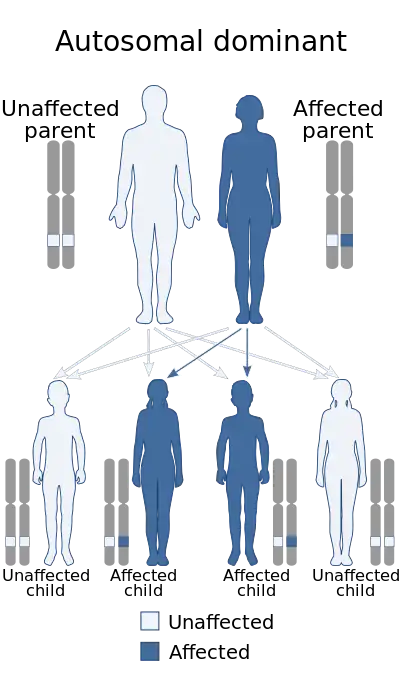

Hereditary hemorrhagic telangiectasia (HHT), also known as Osler–Weber–Rendu disease and Osler–Weber–Rendu syndrome, is a rare autosomal dominant genetic disorder that leads to abnormal blood vessel formation in the skin, mucous membranes, and often in organs such as the lungs, liver, and brain.[1][2]

It may lead to nosebleeds, acute and chronic digestive tract bleeding, and various problems due to the involvement of other organs. Treatment focuses on reducing bleeding from blood vessel lesions, and sometimes surgery or other targeted interventions to remove arteriovenous malformations in organs. Chronic bleeding often requires iron supplements and sometimes blood transfusions. HHT is transmitted in an autosomal dominant fashion, and occurs in one in 5,000–8,000 people in North America.[1][2]

HHT is a genetic disorder with an autosomal dominant inheritance pattern. Those with HHT symptoms that have no relatives with the disease may have a new mutation.[7] Homozygosity appears to be fatal in utero.[1]